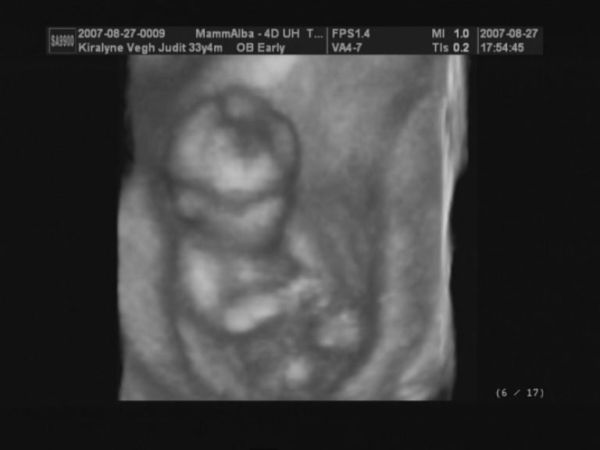

4D képek

Kép

Nagyon édes a babó,nagyon szépen látszik a képeken!!!!!

És olyan de olyan helyes kismanó van a pocidban!! :lol:

Köszönöm a dícséreteket a kicsikémre. Annyira jó volt látni, hogy mindene megvan, és mindenből annyi van amennyinek lenni kell.

Egy kicsit csalódott vagyok ugyan, hogy nem tudta megmondani 100%-ra, hogy fiu-e vagy lány, de a jelenleg nincs kuki elég bíztató.

Nagyon édes a baba a képeken(szerintem csajszi lesz,olyan szép!! :wink: )

gyönyörűek vagytok mindnyájan! Az egyik képen mintha szopná az ujját, miközben hátonfekszik keresztbe tett lábbal és feje alatt a másik keze ("napozik", 2D-s kép oldalról) :lol: